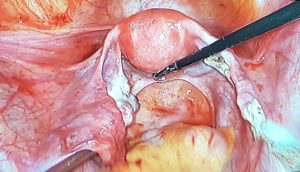

Treatment: Bilateral laparoscopic cystectomy was done under general anesthesia.

Intraoperative findings: Left-sided twisted dermoid cyst of 12×10 cm, right sided dermoid cyst of 12×8 cm with another small simple cyst. Capsules were intact bilaterally, without adhesions; no free fluid. Bilateral tubes seemed normal. Uterus was anteverted and normal in size. Cut- section: Dermoid cyst contained hair, sebaceous fluid, and cheesy material.